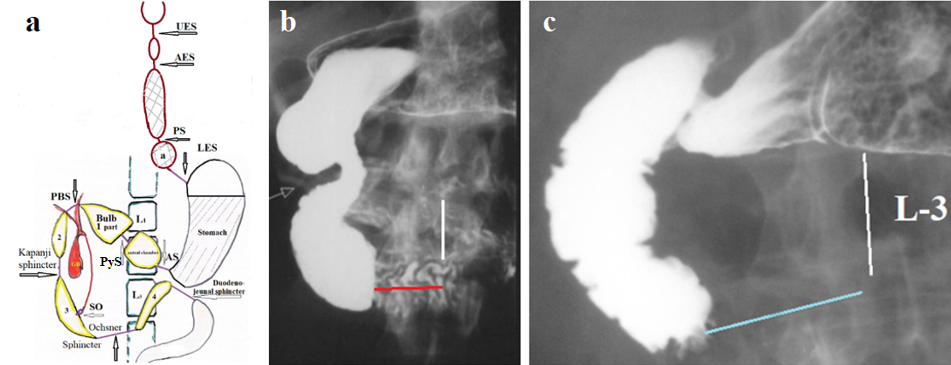

In the duodenum, four sphincters function, which protects the small intestine from the aggressive effects of hydrochloric acid. If the bolus passed through the duodenum as quickly as it passed through the esophagus, the extremely low pH bolus could cause damage to the jejunum. The post bulbar sphincter (PBS), together with the pyloric sphincter (PS), provides evacuation of the chyme from the stomach as portions of a certain volume (Figure 3 A). When the acid bolus reaches the Ochsner’s sphincter, which is in the 3rd part of the duodenum, it causes its contraction, which prevents entering aggressive chyme to the jejunum (Figure 3 B). As a result of the Ochsner’s sphincter contraction, the bolus is thrown cranially, but Kapanji’s sphincter contraction [12], bolus is again thrown в towards the Ochsner’s sphincter. This pendulum movement of the bolus between the Ochsner and Kapanji sphincters occurs several times. During this time, the chyme mixes with bile and pancreatic juice, which raises the pH of the chyme. When the pH reaches a level that is safe for the jejunum, Ochsner’s sphincter opens, and bolus passes into the jejunum [4, 12,13,14]. On a standard x-ray study, barium passes through the duodenum without delay because it has a high pH. When vitamin “C” was added to barium, we found a contraction of the Ochsner and Kapandji sphincters and were able to determine their sizes (Figure 3 C) [13]. Radiographic measurements длины of the Ochsner's sphincter (3.20 ± 0.15 cm) were in complete agreement with the anatomical length of the sphincter described and measured by Ochsner (3.30 ± 0.15 cm) (P > 0.2). Our results were the same in length, location, and function. They have been published repeatedly in the open press [4, 12,13,14] and have not been refuted.

Figure 3. X-ray demonstration of the duodenal sphincters. (a) During antral contraction of the stomach, the duodenal filled to the limit, after which the pyloric sphincter (PyS) contracts, stopping the flow of barium from the stomach into the bulb. Then, during the peristaltic contraction of the bulb between the PyS and postbulbar sphincter (PBS), the pressure rises, which causes the PBS to relax, and the bolus penetrates the 2nd part of the duodenum. (b) In a patient with duodenal dyskinesia, the white arrow indicates the location of the PBS. An expansion of the duodenum is determined between the Kapanji’s sphincter (pink arrow) and the Ochsner’s sphincter (blue arrow). (c) The duodenum was emptied, but the barium remained in deep folds because the barium-filled bowel was very wide. Two zones of contraction with longitudinal folds are visible: [a] the Kapanji’s sphincter, and [b] the Ochsner’s sphincter. The juxtapapillary diverticulum [d] is located between them. These diverticula result from the extrusion of the mucosa between the muscular fibers. Thus, this diverticulum is evidence of high pressure that occurs between contracted sphincters Kapanji and Ochsner.

Hypersecretion of hydrochloric acid causes dyskinesia of the sphincter of Ochsner, manifested by hyperplasia of muscle fibers and increased spasm. This leads to increased pressure in the duodenum above the contracted sphincter. Dilation of the duodenum is evidence of this phenomenon. Dyskinesia of the sphincter of Ochsner causes two pathological phenomena: a) High pressure in the duodenum impairs bile flow, which subsequently leads to bile stagnation in the gallbladder, its concentration increases, and the formation of stones. Gradually, the common duct dilates. To overcome the high pressure in the SO and duodenum, a functional sphincter forms in the dilated common duct above the last peristaltic wave. Between it and the SO, a bilaterally closed ampulla develops. The advancing peristaltic wave increases the pressure in the ampulla, which leads to the SO opening, and the ampulla injects its contents into the duodenum. Retrograde movement in the common duct occurs only in pathological conditions. If, during contraction of the ampulla, the sphincter above the ampulla opens, unable to withstand the pressure, then the contents of the duodenum enter the common duct. This is the only pathway for microbes to enter the bile ducts, leading to acute cholecystitis. b) High pressure in the duodenum with a spasmodic Ochsner sphincter leads to duodenogastric reflux (Figure 5).

Figure 5. (a) Diagram of the sphincters of the upper gastrointestinal tract. Abbreviations: Anatomical sphincters: UES – upper esophageal sphincter; LES- lower esophageal sphincter; PyS – pyloric sphincter; SO – sphincter Oddi. Functional sphincters: AES - Aorto-esophageal sphincter; PS- Proximal sphincter; AS - Antral sphincter; PBS – Post bulbar sphincter; Kapandji sphincter; Ochsner sphincter; duodenojejunal sphincter. (b) Radiograph from the article by Neri et al., showing duodenal dyskinesia manifested by contraction of the Ochsner sphincter (red line), moderate intestinal dilation, and insufficiency of the Kapandji sphincter (arrow). Despite the absence of obstruction, the authors cited this case as a typical example of superior mesenteric artery syndrome [20,21]. (c) Contraction of the Ochsner sphincter promotes bolus reflux into the stomach. This is the mechanism for duodenogastric reflux. Our observation.